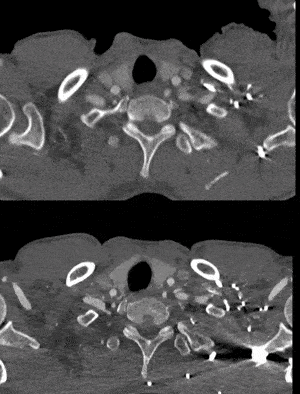

02. 沿左肱动脉穿刺并引入标记导管于升主动脉造影,见左椎动脉优势明显,LSA与LCCA距离小于10mm。

04. 沿左肱动脉引入5F Ver导管,头端垂直抵住主体支架覆膜,引入0.035″长泥鳅导丝配合导管顺利破膜,进入主动脉。

郎德海教授团队在本案例中优先选用华脉胸主支架进行治疗,左肱动脉仅穿刺并引入0.035″长泥鳅导丝配合Ver导管轻松完成破膜操作,并采用牵张导丝,沿股动脉入路引入LSA开窗支架完成对LSA的重建,避免了常规开窗左肱动脉切开的操作。华脉泰科胸主动脉覆膜支架展现了精准的近端定位能力,其开窗处覆膜设计兼具易穿透性和易扩张性,结合0.035″泥鳅导丝软头可快速完成破膜,球囊扩张开口过程简便且安全可靠。支架植入后形态理想,病变封闭效果显著,无膜漏发生,治疗效果明确,患者预后良好。